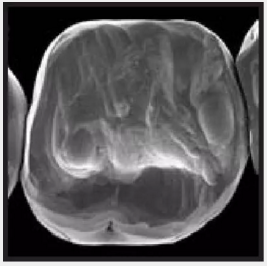

復(fù)合樹脂在即刻充填后,觀察其在電子顯微鏡下的掃描圖像,本次研究選擇了9種具有代表性的復(fù)合樹脂材料。

4.png

Filtek LS 3M ESPE